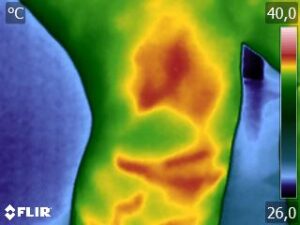

Como no caso da sequência de termogramas abaixo de uma paciente do sexo feminino, 42 anos, sem comorbidade e que apresentou dor em joelhos após treino de musculação. Foi realizado uma Análise Termofuncional e detectado alterações térmicas condizentes com o relato de dor.

Estas informações foram a oportunidade para convencer a paciente a realizar uma ressonância magnética para determinar o grau de comprometimento tecidual. Pois sem isso, após a melhora da dor, a liberação de carga e até a carga terapêutica ficariam limitadas.

Já com este conhecimento foi possível determinar um tratamento que abarcasse as áreas de dor e as áreas de comprometimento tecidual que apresentam inflamação, até a paciente retornar com o resultado da ressonância.

Isso adianta e muito a reabilitação, pois oferece informação que a olho nu não seria possível.